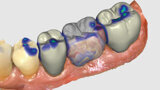

Fig. 4: Bridge design using CEREC Software.

Fig. 5: Bridge design using CEREC Software.